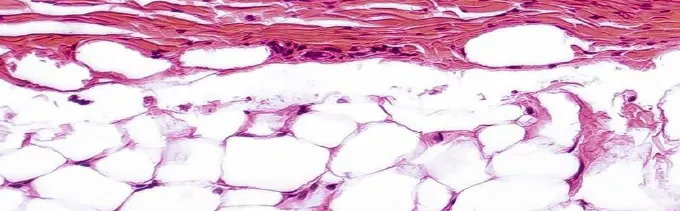

传统修护聚焦物理屏障(皮脂膜+角质层),但皮肤真正的防御体系是三重屏障(物理屏障、免疫屏障、微生态屏障)的组合。

内源性衰老的各种途径(氧化应激、端粒、炎症、DNA 损伤等)的源头都是指向线粒体的功能障碍。

线粒体功能障碍会引起 ROS的过量产生,值得提的是内源性ROS的主要来源就是线粒体。

年龄增长、紫外线、压力都会导致线粒体功能障碍,引发ROS过量产生,开启炎症通路——这才是敏感反复的底层密码。